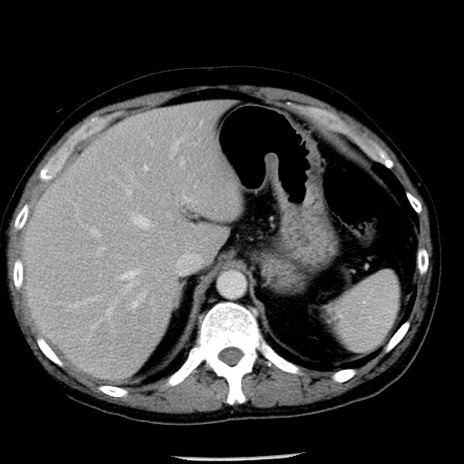

冠状断像

【症例】40歳代男性

【現病歴】2日前から胃痛あり。徐々に周期的な激痛に変化した。本日になっても激痛があるため受診。

【身体所見】意識清明、BT 38-39℃台あり、腹部:膨満、やや硬、右下腹部に圧痛あり。

【データ】WBC 8500、CRP 23.26